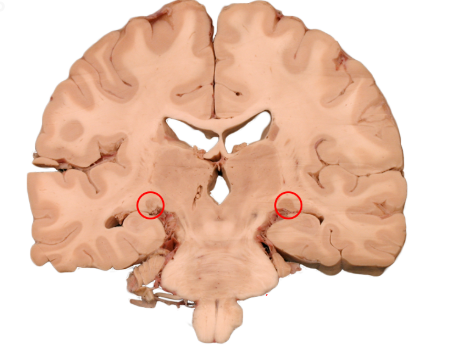

Lateral Geniculate Nucleus (LGN)

A structure in the thalamus that is the relay/processing center for visual information.